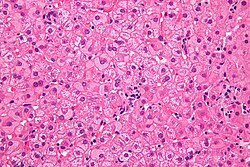

Histopathologisch charakteristisch für eine chronische Hepatitis-B-Infektion sind sogenannte Milchglashepatozyten.[34] Aufgrund der Hyperplasie des glatten Endoplasmatischen Retikulums (sER, von englisch smooth), induziert durch eine massive Vermehrung des Virushüllmaterials (HBs-Antigen), erscheint das Zytoplasma dieser Leberzellen unter dem Mikroskop blass-eosinophil, feinstkörnig, homogen-milchglasartig.[35] Demgegenüber müssen bestimmte andere Formen der Hyperplasie des sER abgegrenzt werden, wie sie durch Medikamenteninduktion (Disulfiram, Barbiturate) oder andere Krankheitsbilder (z. B. Lafora-Krankheit) entstehen können. Im akuten Stadium der Hepatitis B sind Milchglashepatozyten nicht nachweisbar.[34]